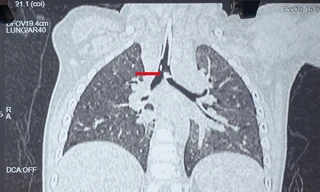

TPO - Suốt 20 năm ho ra máu dai dẳng nhưng không tìm ra nguyên nhân. Gần đây, tình trạng chuyển nặng, người bệnh đến TPHCM thăm khám thì được bác sĩ phát hiện có dị vật lớn nằm trong phế quản.